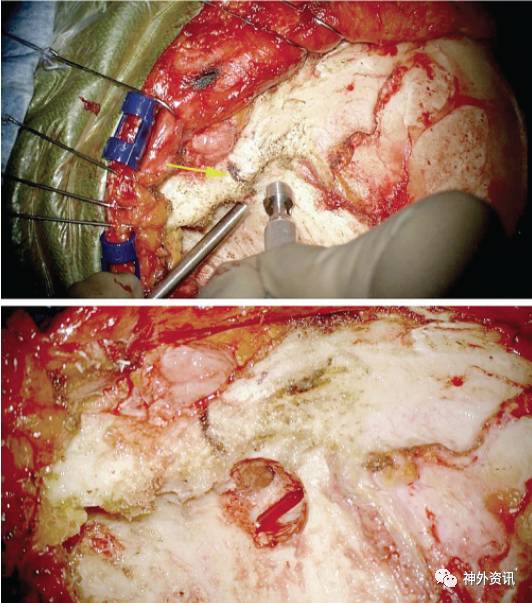

图20:眶颧开颅需钻两个骨孔。必要时可钻更多的骨孔以保证硬膜的完整。第一个钻孔位置恰位于颞上线尾侧、靠近骨面后缘处。注意使用鱼钩牵开器最大程度地牵开软组织;颞肌向下而非向前牵开。

图21:必须正确定位关键孔并按正确的角度进行打磨,才能透过该孔同时显露眶骨膜和额叶硬膜。准确完成此步骤,是顺利进行单骨瓣法眶颧开颅的关键,同时亦可避免关键孔区过多的骨质缺损带来的容貌缺损问题。

关键孔置于颞窝内,大致定位于额颧缝(黄箭)上方7mm、后方5mm处。钻头方向与颞骨所在平面呈45°。通过该孔的后上半可显露额叶硬膜,前下半可显露眶骨膜(插图),两部分由眶顶分隔。